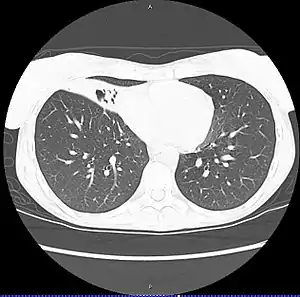

Infecção por Mycobacterium avium-intracellulare (MAI) ou Síndrome de Lady Windermere é uma infecção pulmonar bacteriana causada por um complexo de bactérias oportunistas Mycobacterium avium e Mycobacterium intracellulare que afeta principalmente imunodeprimidos. Afeta 4 mulheres para cada homem afetado, sendo mais comum após os 50 anos ou em crianças com menos de 4 anos. [1]